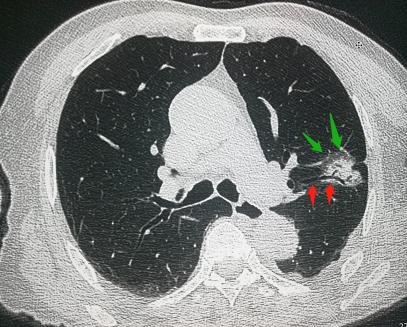

今天确诊的第二例肺癌患者,是一位92岁的老爷子,在家门口摔了一跤,胸口疼,孩子护送着来做胸部CT:

老爷子断了一根肋骨,不严重,休养一阵、预防感染就好,但同时,竟发现了周围型肺癌。

这个病灶跟上面的病人类似,也是混合磨玻璃密度结节,伴有胸膜牵拉,直径2.4cm。

我们再细看这个病灶:红色箭头区为管状的支气管充气征,在肺腺癌病灶中见到支气管充气征,常提示肿瘤分化良好,提示预后较好;另外,病灶边缘的磨玻璃影在病理上属于贴壁生长,也是一种高分化。

一般来说,从病理角度,贴壁生长代表高分化,乳头样和腺泡样生长代表中分化,微乳头样和实性生长代表低分化。

所以这个病灶可以谨慎观察,暂不处理。

这个病灶应该已经存在好几年了,现在还没有任何症状。